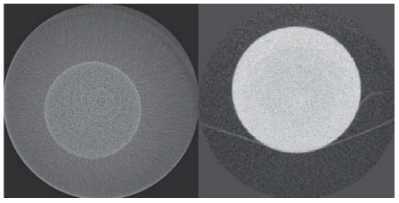

In this work, we propose a novel 4D reconstruction method for PET which is based on spatiotemporal total variation (ST-TV). The ST-TV method takes advantage of image redundancies in 4D and was efficiently implemented using the split Bregman formulation, which has been shown to be optimal for decreasing noise while maintaining image quality. To evaluate the proposed approach we simulated data for a dynamic numerical phantom with different number of counts to mimic high and low Signal-to-Noise Ratio (SNR) scenarios.

| ABSTRACT | Dynamic PET images suffer from low signaltonoise ratio (SNR), especially for fast contrast uptake measurements due to the small number of counts available in those time frames. In this work, we propose a 4D reconstruction method based on spatiotemporal total variation (STTV) which takes advantage of image redundancies in 4D. The 4D STTV method was efficiently implemented using the Split Bregman formulation, which has been shown to be optimal for decreasing noise while maintaining image quality. To evaluate the proposed approach we acquired listmode data from a NEMA image quality phantom in a preclinical PET/CT scanner. |

Scattered photons highly degrade the quality of X-ray images and their effect has become more important due to the increasing interest in cone-beam geometry for the acquisition of CT (CBCT) and micro-CT data. The random nature of scatter events and the great influence of the sample suggest that the most accurate methods for their estimation are Monte Carlo (MC) techniques, but their use is usually hampered by the large computation time required to obtain an acceptable estimation of the scattered radiation. We present an approach for scatter correction in CBCT by MC estimation, speeding up the computation by means of general purpose graphic processing units (GPGPU) and developing a framework for the automatic correction and reconstruction of projection data.

It is usually difficult to compare different designs of Positron Emission Tomography (PET) small-animal scanners because of the disparity of measurements protocols. In this work we compare two commercial PET scanners installed at CIEMAT (Madrid, Spain): the ClearPET and the rPET-1, using an assessment procedure that fulfilled the recommendations of the new NEMA NU 4-2008 standard to evaluate small animal PET systems, including spatial resolution, sensitivity, scatter fraction and count losses studies. |